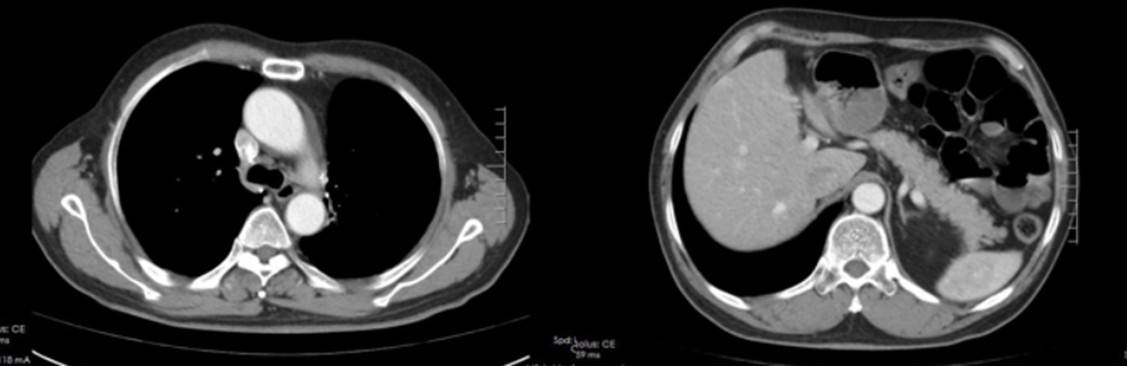

疗效评价:治疗期间定期进行影像学评估,疗效持续达部分缓解(PR):

2023年12月4日(4周期后):左侧锁骨上区、纵隔及左肺门区多发淋巴结转移瘤较前缩小,肝S4转移瘤较前缩小;

截至2025年10月,患者已接受芦康沙妥珠单抗治疗超24个月,PFS达24个月以上,仍在持续治疗中,疾病控制稳定。